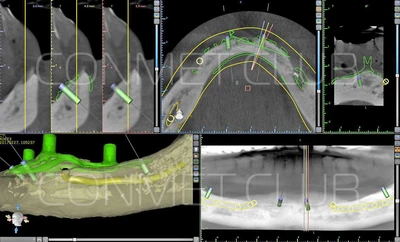

1. Пациенту было произведено МСКТ исследование нижней челюсти, с последующим созданием STL модели. В зуботехнической лаборатории был изготовлен восковой шаблон с искусственными зубами с учетом индивидуальных прикусных взаимоотношений (пока это делает зубной техник точно так же, как при изготовлении съемного пластиночного протеза).

2. После этого произвели компьютерное моделирование самого имплантата и фиксирующих элементов. Примечательно, что в абатментах, использовался отлично зарекомендовавший себя и проверенный десятилетиями интерфейс КОНМЕТ! В результате получили несколько специальных файлов, позволяющих не только сделать сам имлантат, но еще до операции изготовить и сами зубы. Данные файлы передали в изготовление на специальном 3D оборудовании.